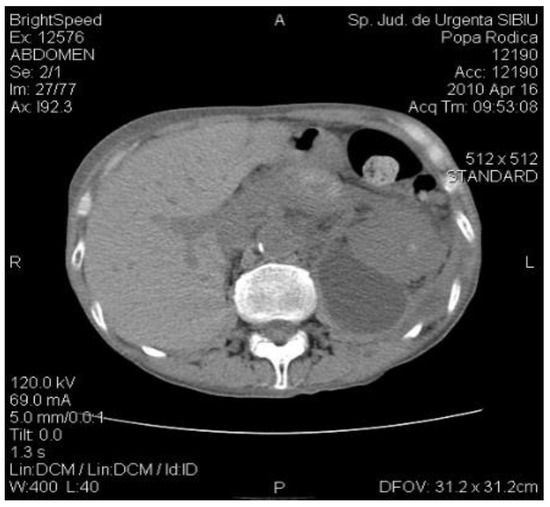

The abdominal CT at follow-up evidenced basal lung segments without changes, normal aspect of the liver, spleen, and kidneys, gallbladder with fluid and homogeneous content, pancreas with small cystic image in the tail, with an irregular contour, with a diameter of 1.9 cm, drainage tubes visible at this level, with an irregular anterior contour of the pancreas at this level, with the dilation of the Wirsung distal from the described formation (Figure 4).

Figure 4.

The CT exam: diminished size of the pancreatic pseudocyst; drainage tubes located in the left renal bed.

Due to the small size of the pancreatic cyst and to the cessation of the drainage on the drainage tubes, it was decided to suppress them.